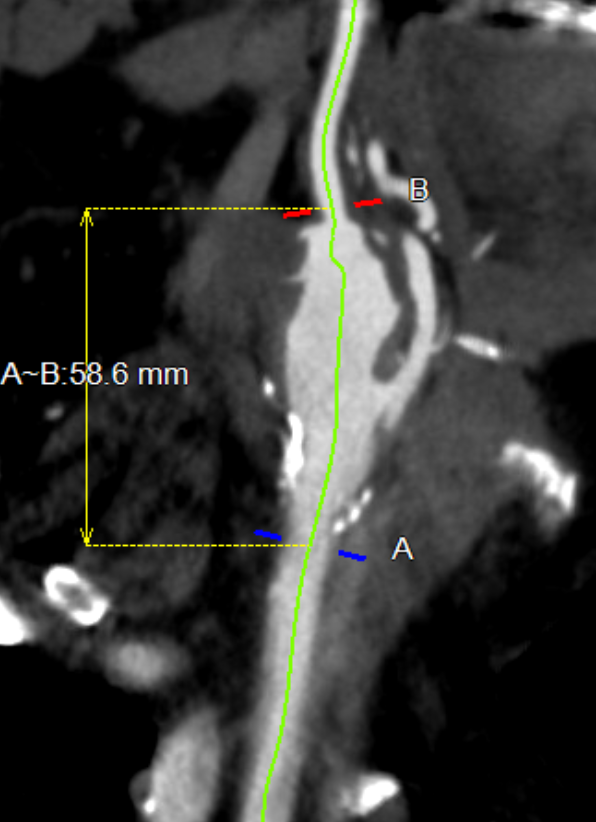

CTA shows the left subclavian artery to be occluded at its origin.

preop sca occlusion.jpg

Heavily calcified occlusive plaque in left subclavian artery

3dvr preop

Arrow points to LSCA origin with plaque